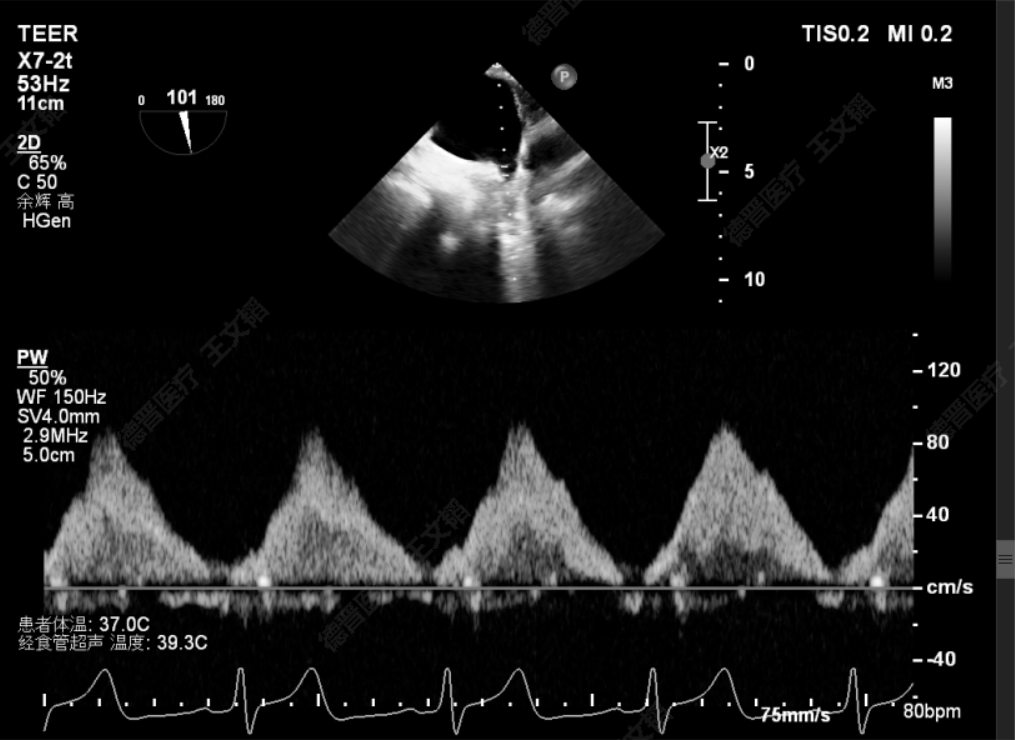

术前静脉逆流

术后静脉逆流

术前潘宏伟教授、何晋教授团队讨论决定,先于2偏1区置入一枚长宽(XW0612)夹解决最大的一处脱垂,再依次向内侧补夹子。术中房间隔穿刺高度:4.4cm,于2偏1区植入一枚长宽(XW0612)夹,夹闭后L侧无残余脱垂。再于M侧2区Side by side植入一枚长宽(XW0612)夹,夹闭后第一枚夹子较前稳定,M侧有残余脱垂。最后于M侧2偏3区植入一枚长窄(XN0412)夹,夹闭后残余功能性反流Trace,压差5mmHg,术毕,反流即刻由术前重度降低为Trace,左房压由术前45mmHg降至术后22mmHg,肺静脉逆流几乎消失,患者明显获益。